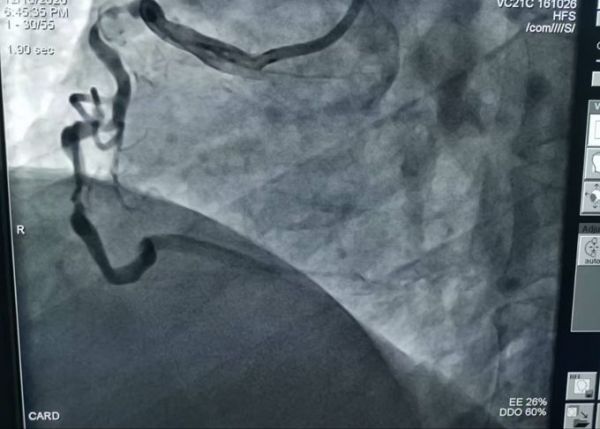

术前造影

接诊后,急诊科医生当即做心电图检查,结果提示异常,便迅速联系心内3病区科会诊。有着多年临床经验的心内3病区主任谭利国通过心电图检测结果、结合患者病史,初步判断患者可能为严重冠心病。

为准确判断病情,建议立即行冠脉造影检查。进一步的冠脉造影结果证实了医生的判断,而检查结果也着实让人揪心:患者三支心脏主血管均存在严重弥漫性钙化病变,且严重狭窄,尤其是其中两根较为严重,最重狭窄为次全闭塞。